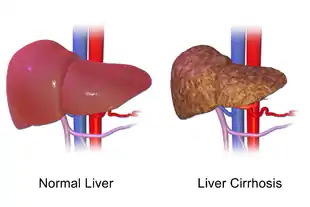

Cirrhosis, also known as liver cirrhosis or hepatic cirrhosis, is a condition in which the liver does not function properly due to long-term damage.[1] This damage is characterized by the replacement of normal liver tissue by scar tissue.[1] Typically, the disease develops slowly over months or years.[1] Early on, there are often no symptoms.[1] As the disease worsens, a person may become tired, weak, itchy, have swelling in the lower legs, develop yellow skin, bruise easily, have fluid buildup in the abdomen, or develop spider-like blood vessels on the skin.[1] The fluid build-up in the abdomen may become spontaneously infected.[1] Other serious complications include hepatic encephalopathy, bleeding from dilated veins in the esophagus or dilated stomach veins, and liver cancer.[1] Hepatic encephalopathy results in confusion and may lead to unconsciousness.[1]

Macroscopically, the liver is initially enlarged, but with the progression of the disease, it becomes smaller. Its surface is irregular, the consistency is firm, and the color is often yellow (if associated with steatosis). Depending on the size of the nodules, there are three macroscopic types: micronodular, macronodular, and mixed cirrhosis. In the micronodular form (Laennec's cirrhosis or portal cirrhosis), regenerating nodules are under 3 mm. In macronodular cirrhosis (post-necrotic cirrhosis), the nodules are larger than 3 mm. Mixed cirrhosis consists of nodules of different sizes.[37]